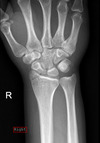

10

Q

A

Colles’ fracture

**Colles - ‘dinner fork type deformity’** Features of the injury 1. Transverse fracture of the radius 2. 1 inch proximal to the radio-carpal joint 3. Dorsal displacement and angulation of the distal radius

**Smith's fracture (reverse Colles' fracture)** 1. Volar angulation of distal radius fragment (Garden spade deformity) 2. Caused by falling backwards onto the palm of an outstretched hand or falling with wrists flexed

Colles vs Smith fracture

Colles fracture ## Footnote Typically FOOSH forwards Extra-articular radial # with dorsal (posterior / back of hand) angulation and displacement

Smith Fracture ## Footnote Typically FOOSH back of hand Extra-articular radial # with volar (anterior / palmar) angulation and displacement